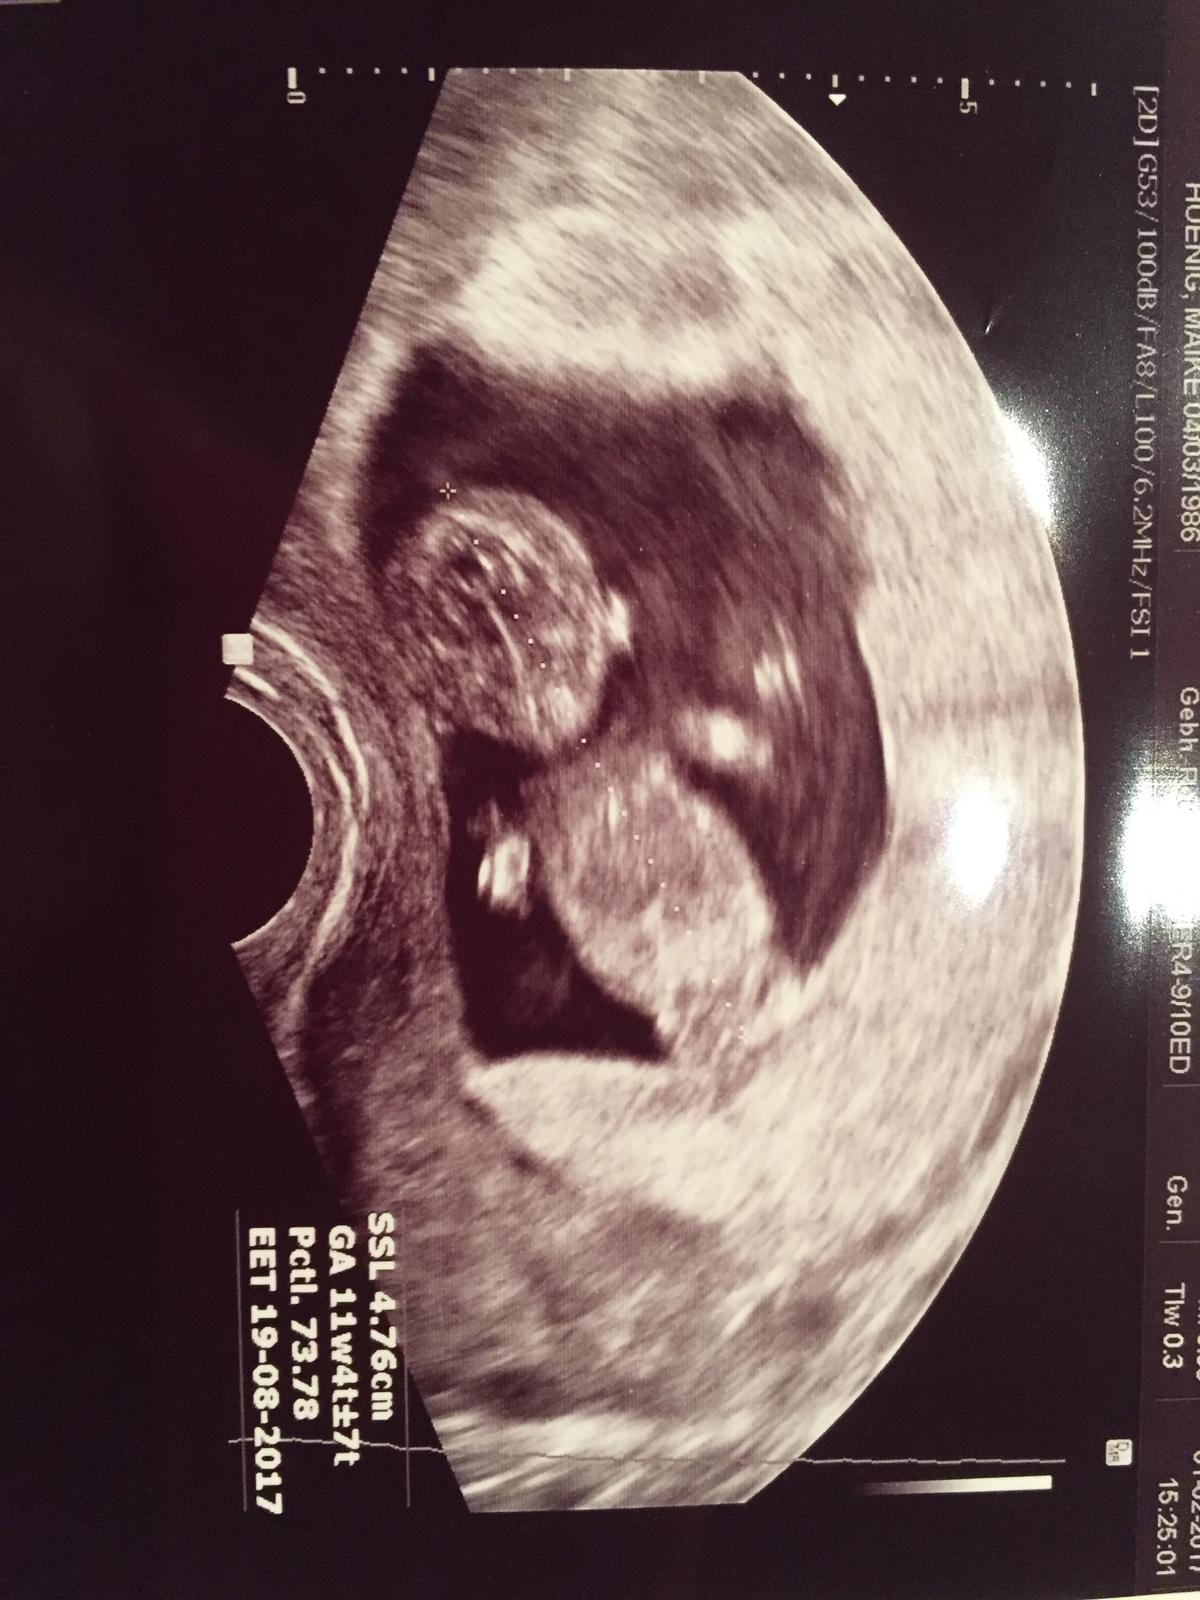

11+2 😍 es kommt halt immer auf die Messung an 😂 Konnte im Ultraschall so viel sehen! Die Ärztin hat sich viel Zeit genommen. Kleine Füße, kleine Ärmchen, Herzschlag.... war anfangs ganz aktiv und ist dann wohl eingeschlafen 😂 wollte sich leider nicht im Profil angucken lassen!

Konnte im Ultraschall so viel sehen! Die Ärztin hat sich viel Zeit genommen. Kleine Füße, kleine Ärmchen, Herzschlag.... war anfangs ganz aktiv und ist dann wohl eingeschlafen 😂 wollte sich leider nicht im Profil angucken lassen!